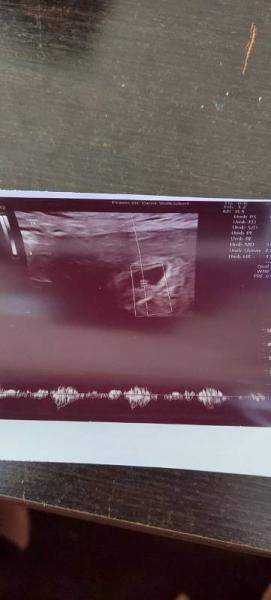

Hallo ihr lieben, sah das bei jemanden auch in der Woche so aus? Es ist kein Dottersack zu sehen & auch kein Embryo habe Angst das es eine Eileiterschwangerschaft ist.

Ganz so früh war ich nicht da aber in der 7ssw da sah es so aus... inkl Herzschlag. Es ist ja eine fruchthöhle zu sehen. Ich denke der Arzt hätte es nun schon gesehen wenn die im Eileiter wäre.

Hallo, Es ist ja eine Fruchthöhle in der Gebärmutter, also wird es keine Eileiterschwangerschaft sein. Dottersack und embryo sollten eine Woche später jedenfalls zu erkennen sein. Liebe Grüße

Mach dir keine Sorgen! Wenn eine deutliche Fruchthöhle in der Gebärmutter zu sehen ist, ist es in der Regel keine Eileiterschwangerschaft.